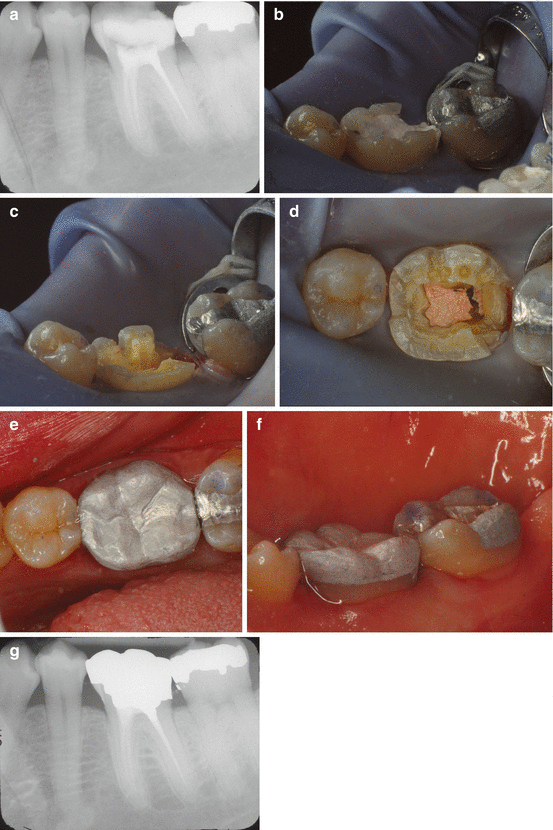

From pocketdentistry.com

Endodontic Considerations for the Restoration of Endodontically Treated Crown Of Teeth Is Covered By In dentistry, crown refers to the anatomical area of teeth, usually covered by enamel. A dental crown is a cap placed on top of a tooth to restore the damaged portion or above dental implants to restore function. A crown may be needed when a large dental cavity threatens the. Dental caps can help recover chipped, cracked and decayed teeth.. Crown Of Teeth Is Covered By.